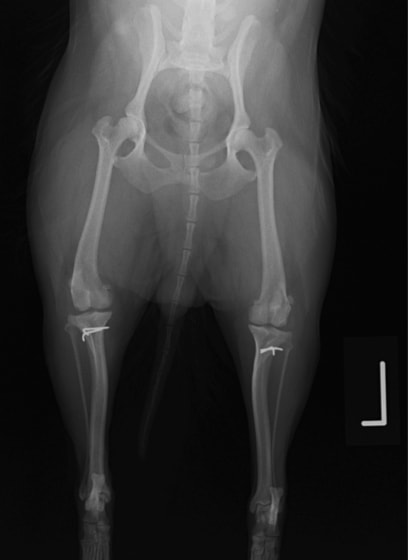

■ 症例22 ポメラニアン 1歳5か月 去勢雄

左後肢の挙上を主訴に来院した。整形学的検査、レントゲン検査より左右の膝蓋骨脱臼(左GradeⅡ〜Ⅲ、右Grade Ⅱ)を認めた。また、脛骨の前方引き出し試験の際に、引き出し兆候は認められないものの、疼痛が認められたため、前十字靭帯の損傷が疑われた。術中における、目視および関節内の操作によって、前十字靭帯の損傷や過伸展といった異常が認められなかったため、膝蓋骨脱臼の整復のみ実施した。手術手技は縫工筋及び内側広筋の解放、脛骨粗面の外側転位、滑車ブロック形造溝術、内外側関節包の縫縮を実施した。本症例は跛行もなく経過良好である。しかし、頸骨高平部の角度(TPA)が 右26.2°、左24.9°であり、解剖学的に前十字靭帯損傷のリスクが高いことから今後の経過に注意が必要である。